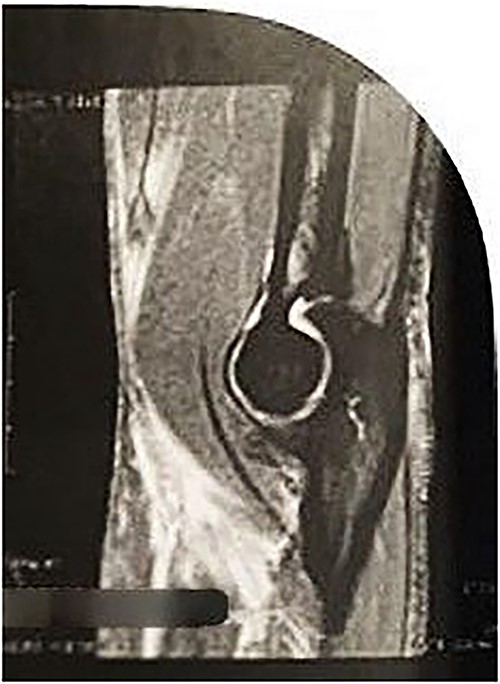

On physical examination (Fig. 1), the patient exhibited a visible deformity of the arm (inverted Popeye sign), a positive Hook test for distal biceps injury, symmetric elbow flexion strength, slightly decreased supination strength with pain, but with a complete range of motion for passive and active pronation-supination and flexion-extension. Ultrasonography and magnetic resonance imaging revealed a complete rupture of the distal biceps tendon (Figs 2–4).

Sagittal MRI Image revealing discontinuity of the DBT and edema in the insertion region.